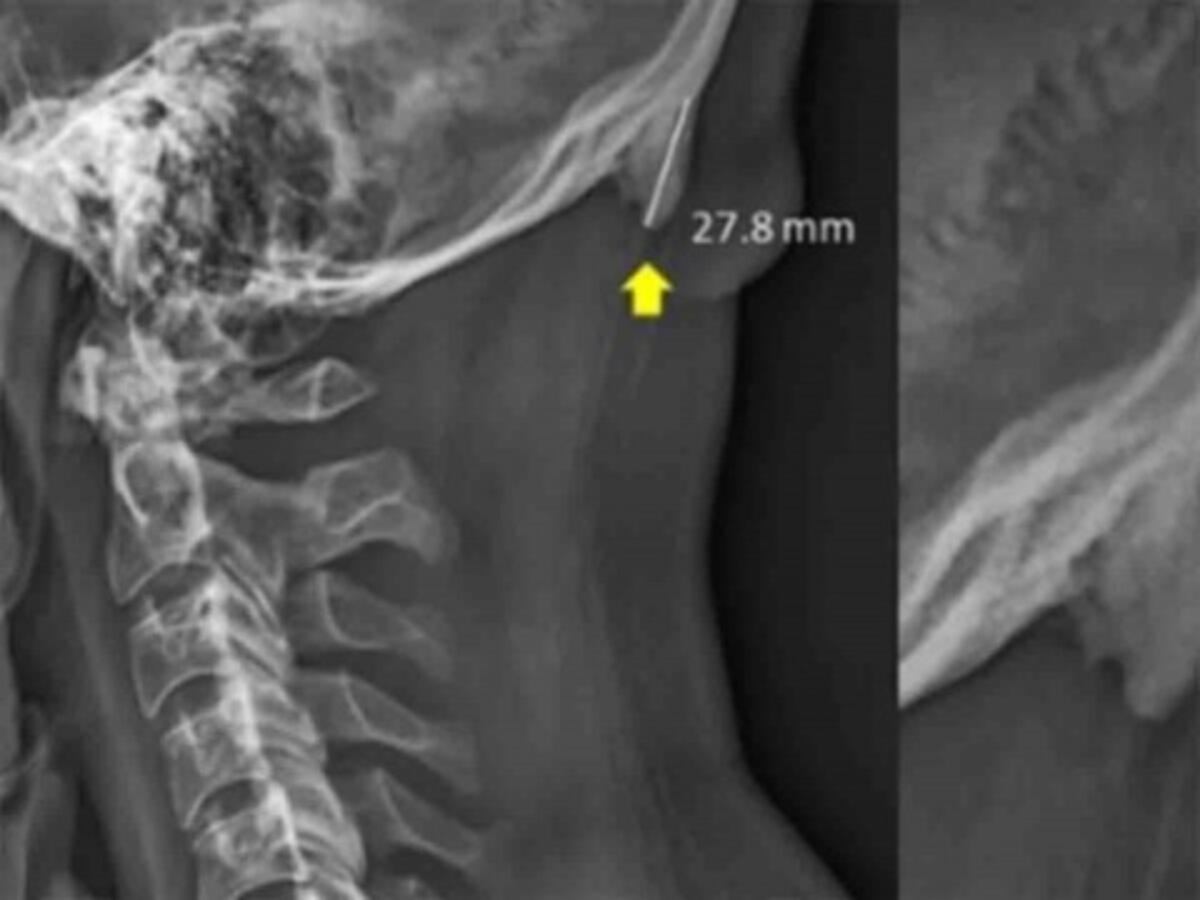

David Shahar, científico encargado de la investigación, reveló que existe una tendencia al crecimiento de una pequeña protuberancia en forma de pico en el cráneo humano.

Este bulto, indica, puede sentirse al tacto y, con la calvicie, puede resultar visible a simple vista.

Para el año 2018, el científico examinó a mil 200 personas determinando que esta ‘malformación’ aparece en mayor medida entre los 18 y 30 años de edad.

Shahar afirma que esto es debido a la inclinación que ejercemos para poder ver las pantallas de nuestros celulares pues, existe esto tensa los músculos para sostener la cabeza que tiene un peso aproximado de unos 5 kilogramos.

Con esta presión ejercida durante mucho tiempo se puede provocar la aparición de este pico, afirmó el científico.